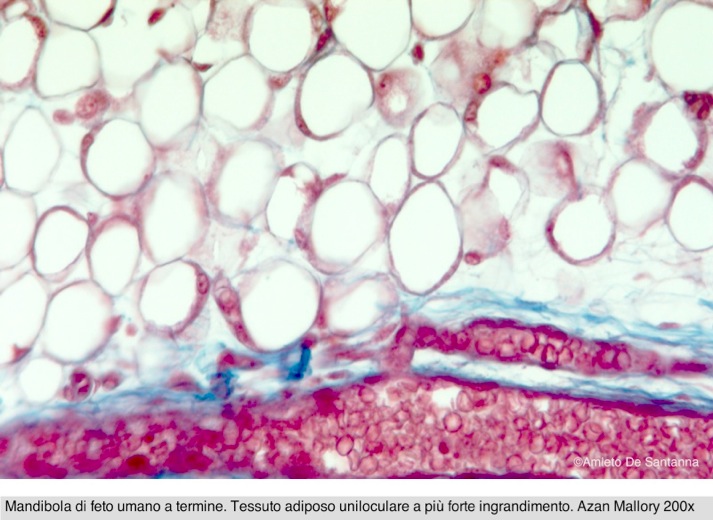

Sulla base della loro ricerca, gli scienziati suggeriscono che quando i ceramidi si accumulano, il tessuto perde le caratteristiche di grasso bruno,diventando sempre più grasso bianco. Questo scatena una sequenza di eventi che possono portare a diverse malattie.